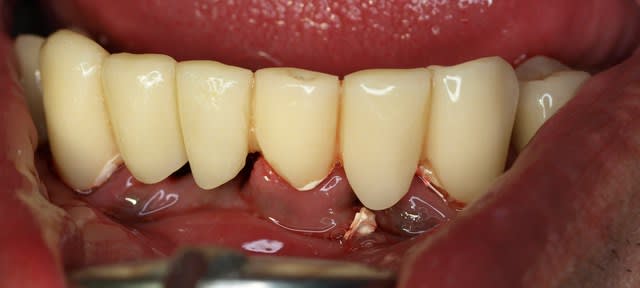

ha ben tiens voila les photo de l'epoque ou je l'ai connu . entre temps il s'est barré voir un aute cd un peu implanto mais pas trop qui lui a viré tout le haut ...